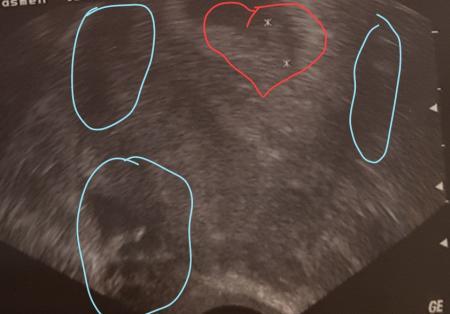

Kurz gefasst ich bin ja 6+6 im Herz ist mein wurm aber was sind die in blau eingekreisten?

Bild zu Direkt ne frage zum Ultraschall - Schwanger - wer noch? Rund um die Schwangerschaft

ich würde mal sagen gewebeflüssigkeit oder auch kleine zysten dies ist normal kann man mal mehr sehen mal weniger für Fruchtblasen wäre es zu weit aussen usw

Ich denke auch, das sind Reflexionen vom Gerät. Es wird ja keine Ebene dargestellt, und im Körper sind ja allerhand Strukturen, wo das Gerät durchschallen muss. Wenn es etwas Auffälliges wäre hättr der Arzt sicher etwas gesagt.